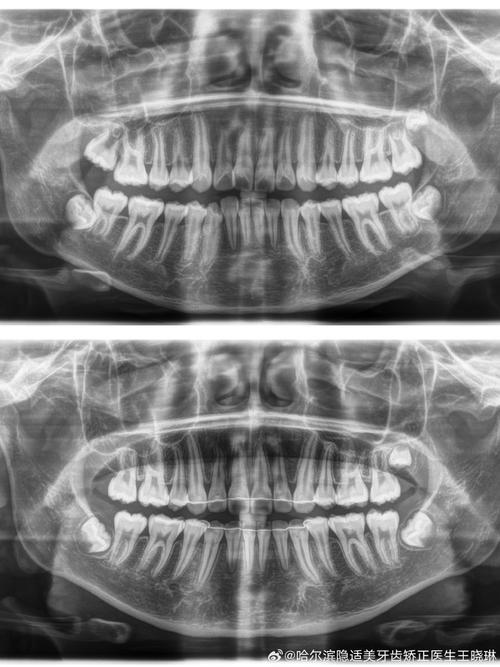

正畸侧位片的拍摄需严格遵循标准化流程:患者采用自然头位,眶耳平面(由眶下缘最低点与外耳道上缘连线构成)与地面平行,X线中心线对准外耳道上方5cm处,胶片或探测器距离中矢面15cm,曝光参数根据患者年龄及体型调整(成人通常为60-70kVp,8-15mA),确保图像清晰显示颅骨轮廓、颌骨形态、牙齿牙根及周围骨结构,避免因头部倾斜、咬合干扰或伪影导致标志点模糊。

正畸侧位片的测量依赖于对关键解剖标志点的识别,临床中通常将标志点分为骨骼与牙齿两大类,共14个核心点(简称“77分析体系”),其定义及临床意义如下表所示:

基于“77分析体系”的标志点,可计算多项关键测量指标,用于评估骨骼型、牙齿位置及软组织侧貌:

骨骼测量指标

- SNA角:由蝶鞍点(S)、鼻根点(N)、上齿槽座点(A)构成,正常值82°±4°,反映上颌骨相对于颅部的位置,SNA角增大提示上颌前突,减小提示上颌后缩。

- SNB角:由蝶鞍点(S)、鼻根点(N)、下齿槽座点(B)构成,正常值80°±4°,反映下颌骨相对于颅部的位置,SNB角增大提示下颌前突,减小提示下颌后缩。

- ANB角:由上齿槽座点(A)、鼻根点(N)、下齿槽座点(B)构成,正常值2°±2°,是判断上下颌骨矢状关系的关键指标,ANB角>4°提示Ⅱ类骨性错颌(上颌前突或下颌后缩),<0°提示Ⅲ类骨性错颌(下颌前突或上颌后缩)。

- SN-Me角:由蝶鞍点(S)、鼻根点(N)、颏下点(Me)构成,正常值68°±5°,反映下颌平面(通过Me点与下颌角点的连线)相对于颅底平面的倾斜度,角度增大提示下颌平面陡峭,面部垂直高度增加;减小提示下颌平面平缓,面部垂直高度不足。

牙齿测量指标

- UI-SN角:上中切牙长轴与SN平面的夹角,正常值105°±6°,反映上中切牙的倾斜度,角度增大提示上切牙唇倾,减小提示舌倾(需注意牙根位置,避免舌倾过度导致牙根吸收)。

- LI-MP角:下中切牙长轴与下颌平面(MP)的夹角,正常值95°±6°,反映下中切牙的倾斜度,临床中常要求下切牙控制在90°-110°,避免过度唇倾导致牙龈退缩或舌倾影响咬合功能。

- U1-NA距:上中切牙切缘至NA连线的垂直距离,正常值4mm±2mm,反映上切牙相对于上颌骨的突度,距离过大提示上切牙前突,需内收;过小提示舌倾,可能需唇展。

- L1-NB距:下中切牙切缘至NB连线的垂直距离,正常值4mm±2mm,反映下切牙相对于下颌骨的突度,临床意义与U1-NA距类似,是下颌切牙矫治的重要参考。

正畸侧位片通过“77分析体系”的量化数据,可实现:①错颌畸形分类(骨性Ⅰ、Ⅱ、Ⅲ类,牙性深覆颌、深覆盖等);②制定个性化矫治方案(如拔牙与否、种植支抗设计、隐形矫治方案规划);③预测矫治后效果(通过计算机模拟分析骨骼、牙齿移动后的位置变化);④评估治疗后稳定性(对比治疗前后指标变化,防止复发),对于ANB角>4°的Ⅱ类错颌患者,若同时伴有U1-NA距过大,需设计上颌磨牙后移、切牙内收的方案;对于SN-Me角过大的垂直生长型患者,需避免使用垂直向牵引,以防面高进一步增加。